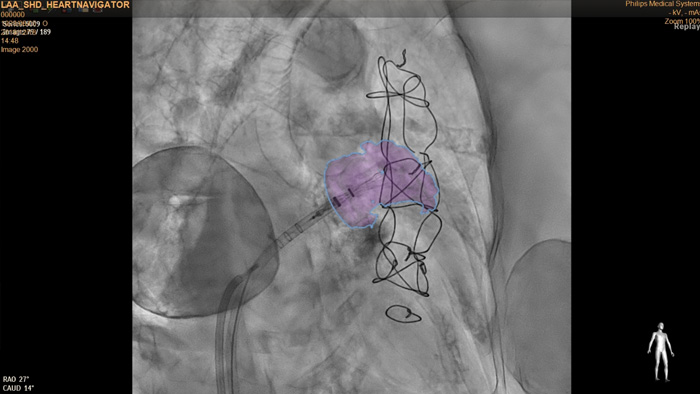

HeartNavigator

The HeartNavigator is a CT planning and live overlay guidance solution using automatic heart model segmentation of anatomy to improve ease of use, speed and reproducibility. In LAA occlusion, HeartNavigator enables: